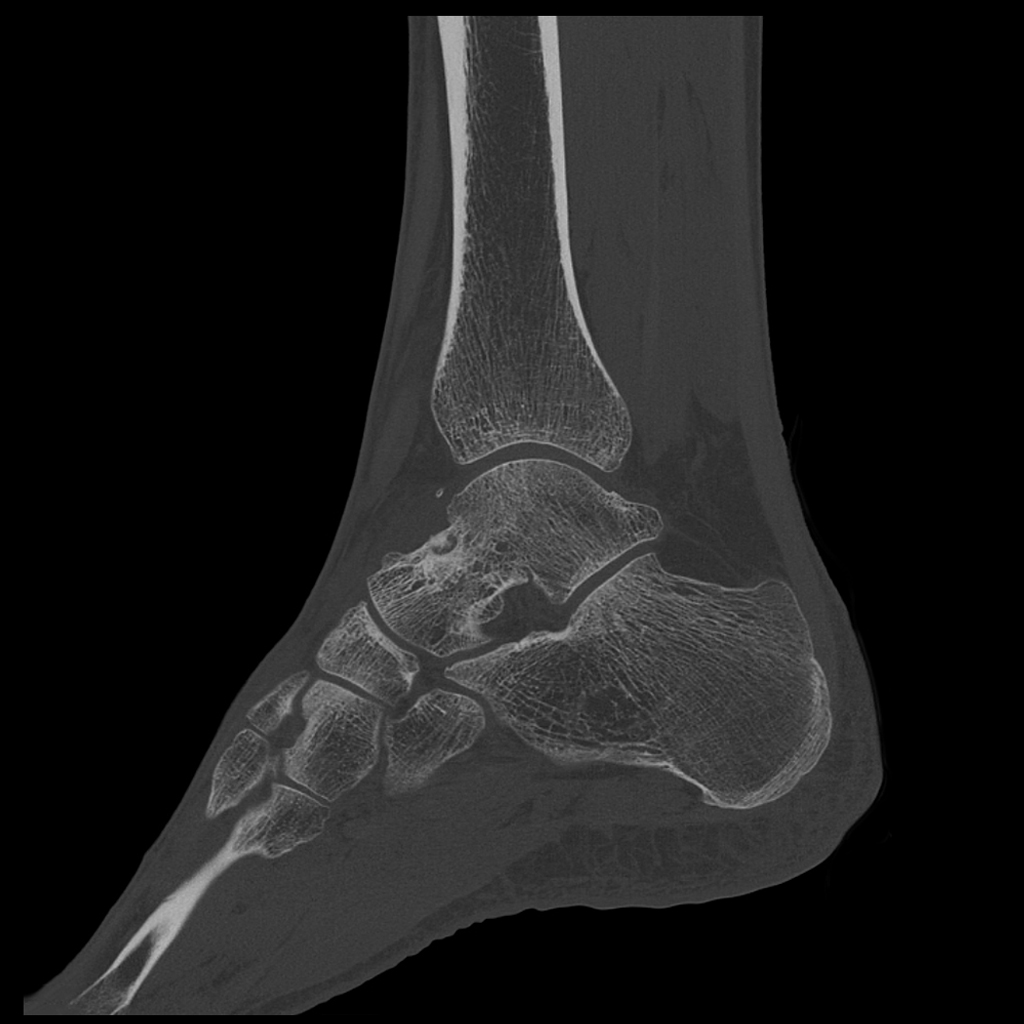

Порівняння звичайної роздільної здатності з ультрависокою роздільною здатністю (УРЗ)²

Звичайна КТ 0,5 мм

КТ з ультрависокою роздільною здатністю 0,25 мм ³